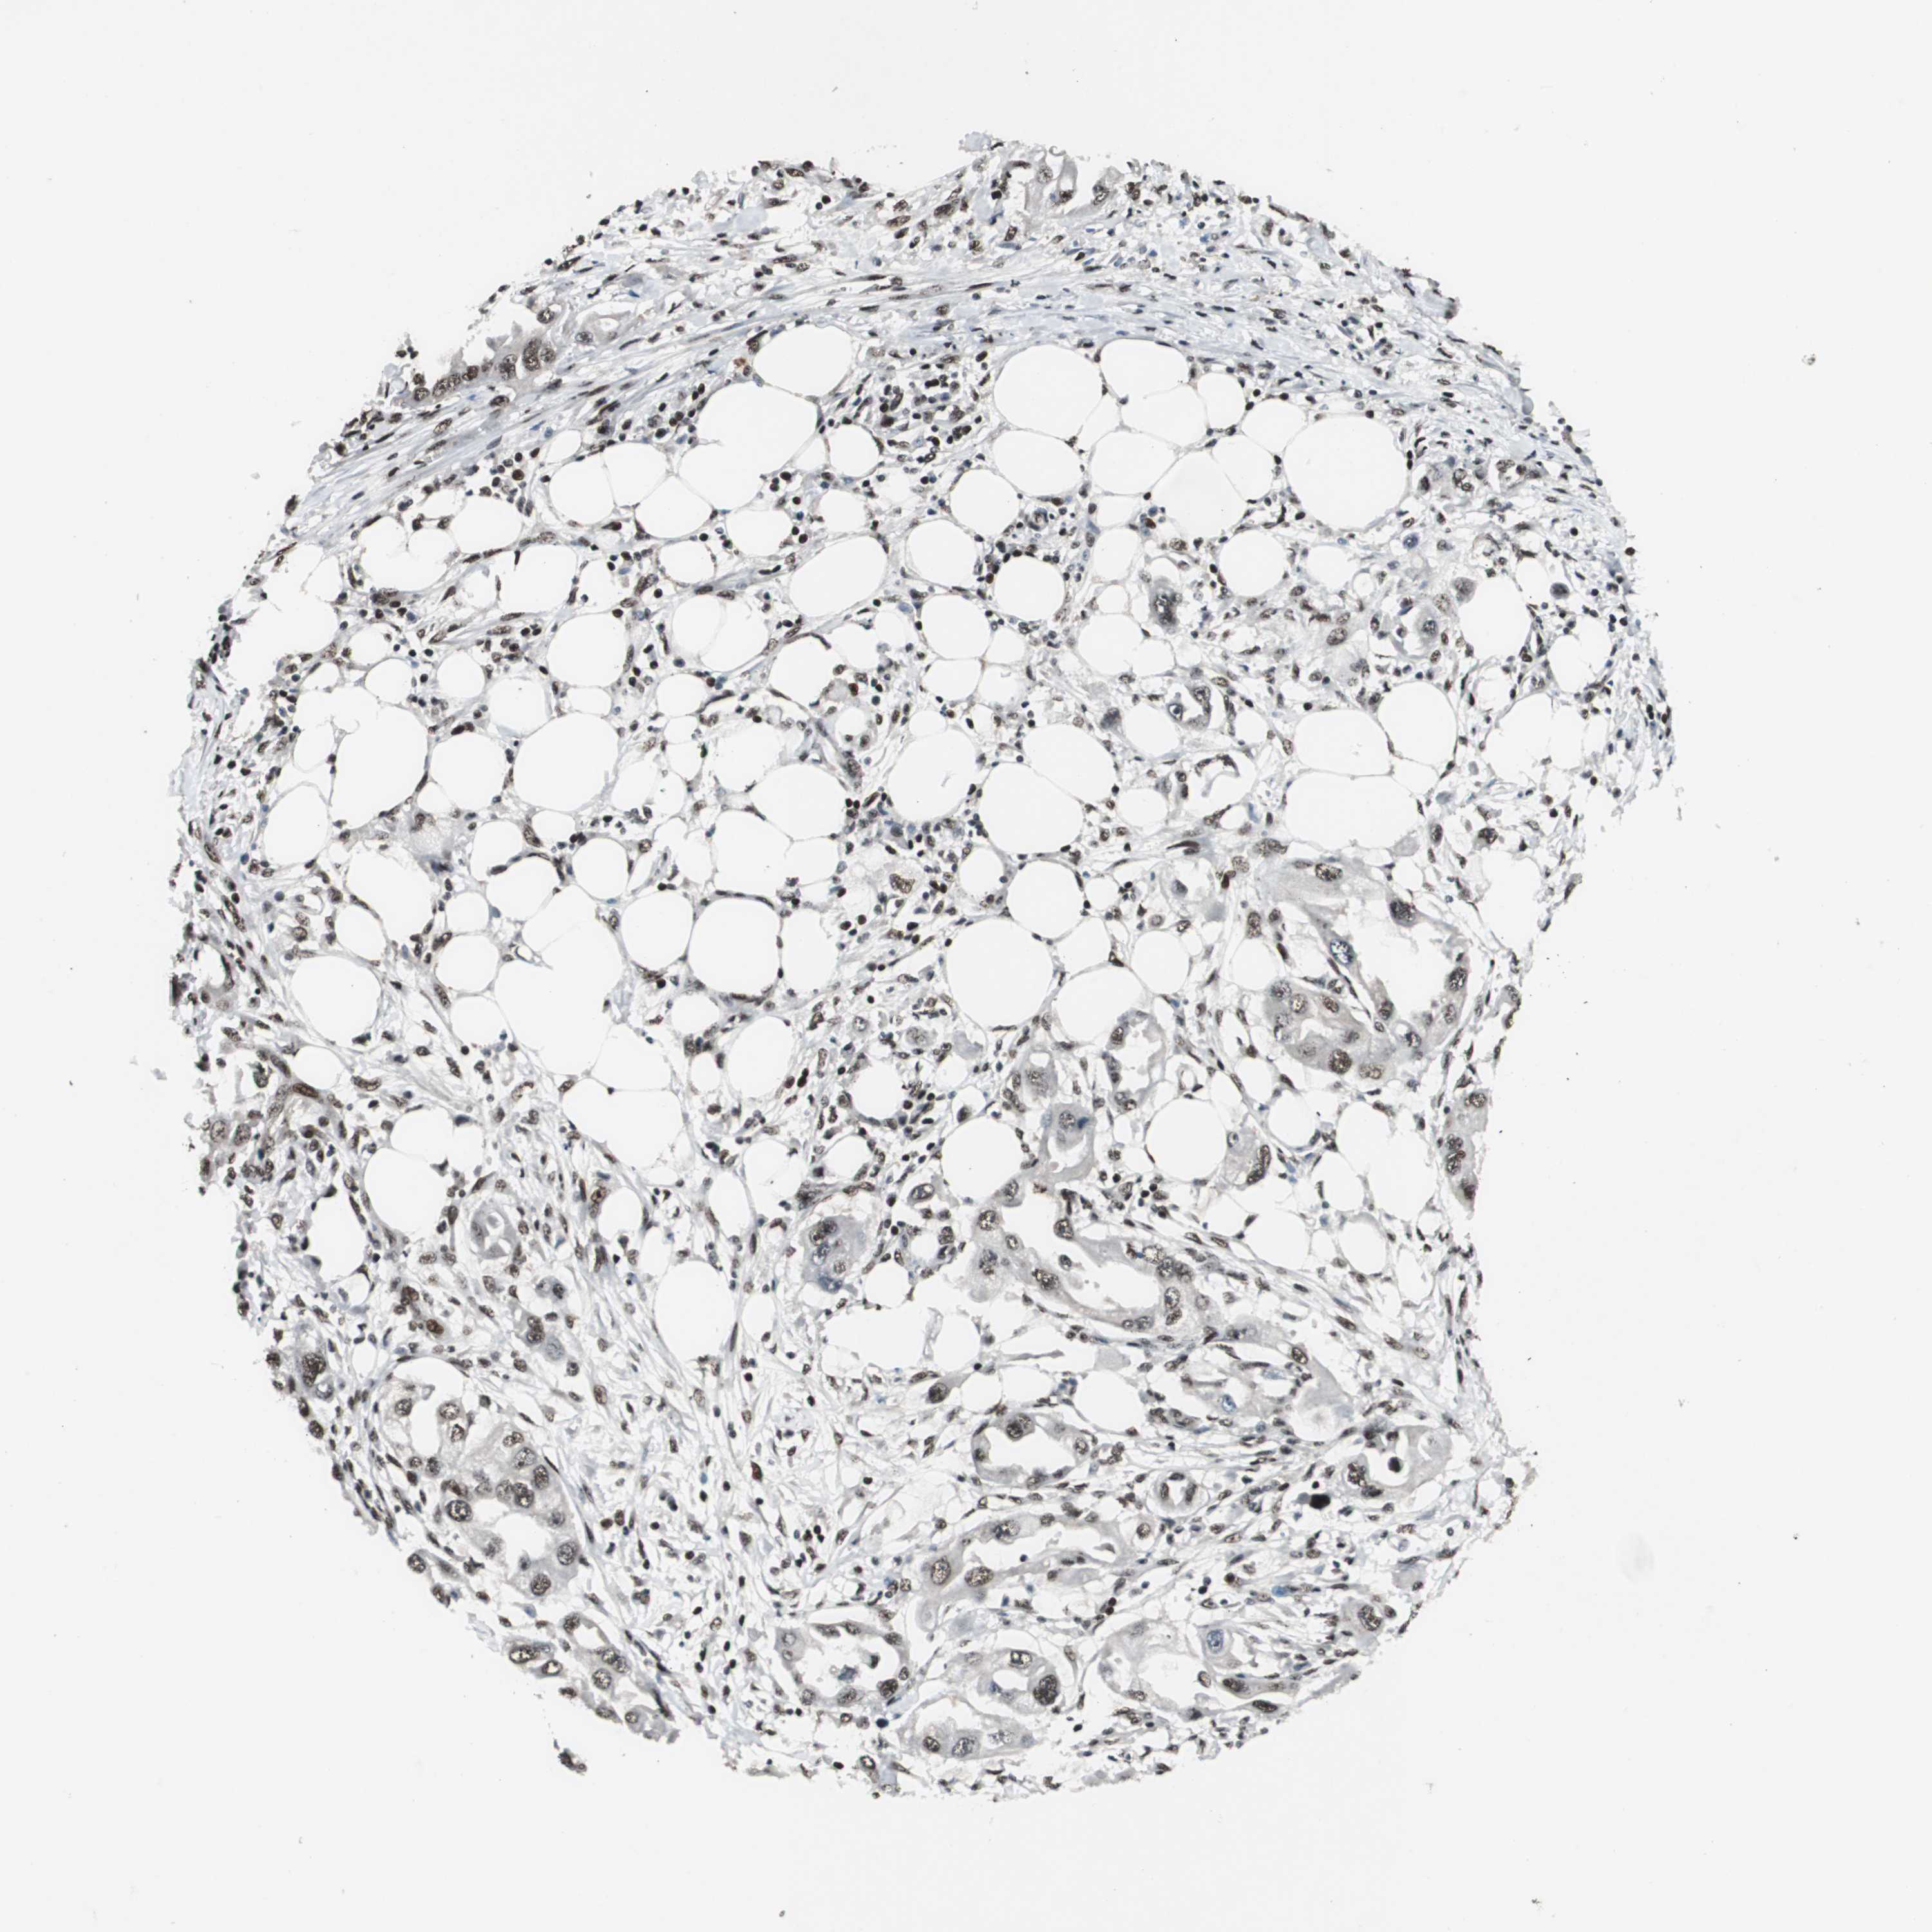

ENDOMETRIAL CANCER - Protein expressioni

A mouse-over function shows sample information and annotation data. Click on an image to view it in a full screen mode. Samples can be filtered based on level of antibody staining by selecting one or several of the following categories: high, medium, low and not detected. The assay and annotation is described here.

Note that samples used for immunohistochemistry by the Human Protein Atlas do not correspond to samples in the TCGA dataset.

Antibody stainingi

Antibody staining in the annotated cell types in the current human tissue is reported as not detected, low, medium, or high, based on conventional immunohistochemistry profiling in selected tissues. This score is based on the combination of the staining intensity and fraction of stained cells.

Each image is clickable and will lead to virtual microscopy that enables deeper exploration of all samples and also displays staining intensity scores, fraction scores and subcellular localization as well as patient and tissue information for each sample.

Antibody HPA006982

Staining

High

Medium

Low

Not detected

Intensity

Strong

Moderate

Weak

Negative

Quantity

>75%

75%-25%

<25%

None

Location

Nuclear

Cytoplasmic/membranous

Cytoplasmic/membranous,nuclear

Adenocarcinoma, NOS